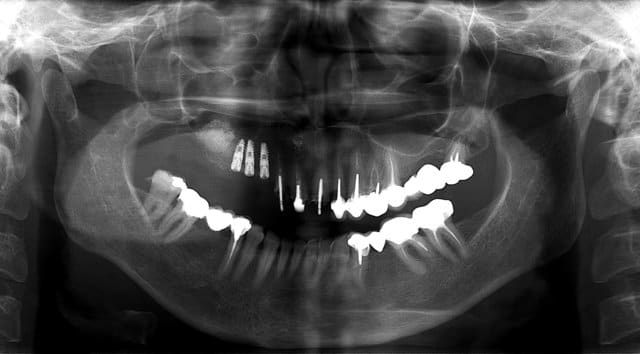

Ce matin je viens de faire une expansion osseuse et un sinus.

J’avais prévenu la patiente que je n’étais même pas sure de pouvoir poser des implants tant les crêtes étaient fines.

Anesthésie -

incision supra -crestal - décharge au niveau de 12-11 - lambeau pleine épaisseur- fenêtre d'accé au sinus- soulevé de la membrane de Schneider- comblement Graftec- membrane Collagen AT - spliting sur la crête osseuse de 15 à 12- légère décharge osseuse au niveau de 12 - expansion osseuse en vestibulaire- pose implants -13-14-15- comblement espace inter implants et en vestibulaire par KASIOS TCP - membrane de recouvrement Collagen AT-

Sutures simples vicryl 5/0 pour la décharge et 4/0 pour la crête.

Opt post op h7qt6p - Eugenol